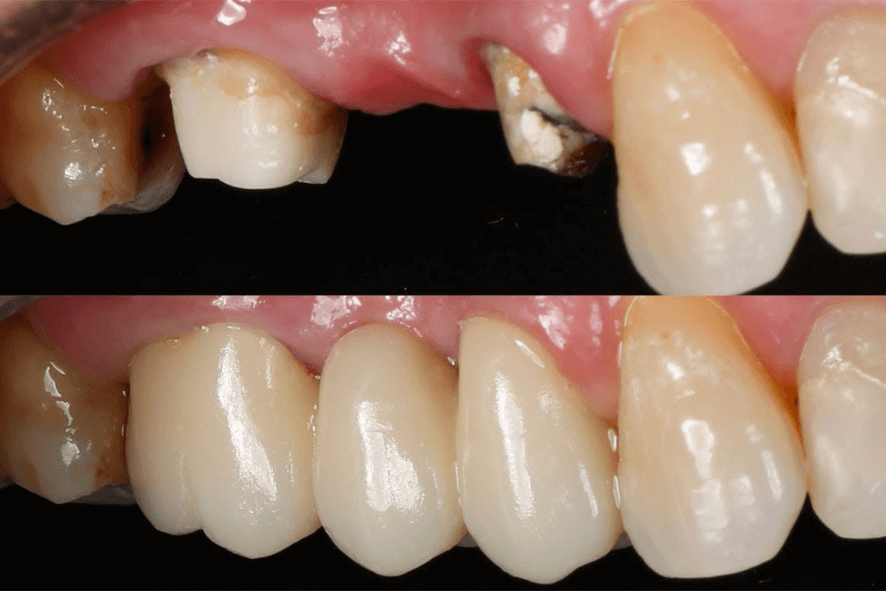

Tipos de próteses fixas

Prótese Fixa: Vantagens e Benefícios

🔹Mais estabilidade e durabilidade

🔹Não precisam ser removidas para higienização

🔹Melhoram mastigação e fala, aproximando-se dos dentes naturais

🔹Quando bem planejadas, devolvem estética e autoconfiança de forma duradoura